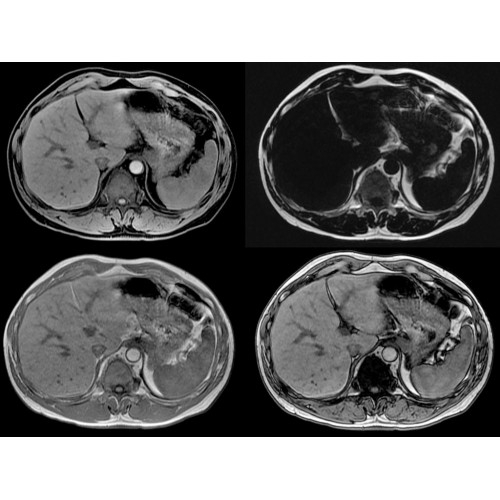

МР-эластография: неинвазивная методика комплектной оценки печени

Пациентам с такими хроническими заболеваниями печени, как фиброз и цирроз, часто требуется регулярное наблюдение гастроэнтеролога. Это может потребовать проведения инвазивных процедур, которые не всегда позволяют получить полную информацию о состоянии печени.

Новая ИП MR-Touch, разработанная компанией GE совместно с клиникой Майо, основана на исследовании печени с помощью акустических волн, в ходе которого выявляются различия в жесткости тканей. Результатом исследования является эластограмма, полное изображение печени. По таким эластограммам радиологи и гастроэнтерологи могут периодически контролировать состояние пациента и принимать информированные решения о терапии. Более того, данная методика открывает новые возможности и позволяет оказывать инновационные услуги имеющимся пациентам и привлекать новых клиентов.